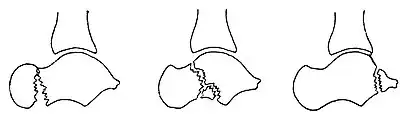

Osul trigon (Os trigonum) (din latina trigonon = triunghi) este un osișor supranumerar (accesoriu) independent al tarsului situat în partea posterioară a talusului, lângă tuberculul lateral al procesului posterior al talusului. Incidența sa a fost estimată în literatura de specialitate a fi între 1,7 și 8% în populație, iar în 1,4% este bilateral. La examenul radiologic, prezența sa trebuie să se distingă clar de fractură Shepherd (fractura tuberculului lateral) care întrerupe baza procesului posterior al talusului. Tendonul mușchiului flexorul lung al halucelui trece medial de osul trigon.[1][8][9][38][52][53][54][55][56][57][58]

După cum sugerează și numele, osul trigon are de obicei o formă triunghiulară, cu 3 fețe (anterioară, inferioară și posterioară), dar poate avea și o formă rotunjită sau ovală. Osul trigon este compus dintr-o parte corticală periferică și un centru spongios. De obicei, osul trigon are trei fețe: una anterioară, alta inferioară și a treia posterioară. Fața anterioară articulară are de obicei o formă de semilună și formează cu tuberculul lateral al talusului o articulație de tip sincondroză sau este legat de acesta printr-un țesut fibros, fibrocartilaginos sau cartilaginos. Fața inferioară, calcaneană, este și ea articulară, și poate să se articulează cu fața superioară a calcaneului, participând la coaliția (sinostoza) talocalcaneană. Fața posterioară este nearticulară. Osul trigon este cel mai adesea unic și măsoară mai puțin de 1 cm pe axul mare. El poate fi, de asemenea, bipartit (divizat în două părți) sau multipartit (divizat în mai multe părți). Osul trigon fuzionat cu tuberculul lateral este numit proces trigonal[14][52][53][59]

Osul trigon provine dintr-un centru de osificare cartilaginas secundar, care se formează în partea posterioară a talusului, între 11 și 13 ani la băieți și între 8 și 10 ani la fete. În mod normal, acest nucleu de osificare fuzionează cu tuberculul lateral al talusului în cursul primului an de la apariția sa, participând la formarea procesul posterior al talusului. Atunci când această fuziune antrenează formarea unui proces talar posterior mare și intact, acesta este numit procesul talar posterior hipertrofic sau "procesul Stieda." În absența fuziunii centrului de osificare cu tuberculul lateral al talusului, din acest centru de osificare se formează un os independent, numit osul trigon.[52][53]